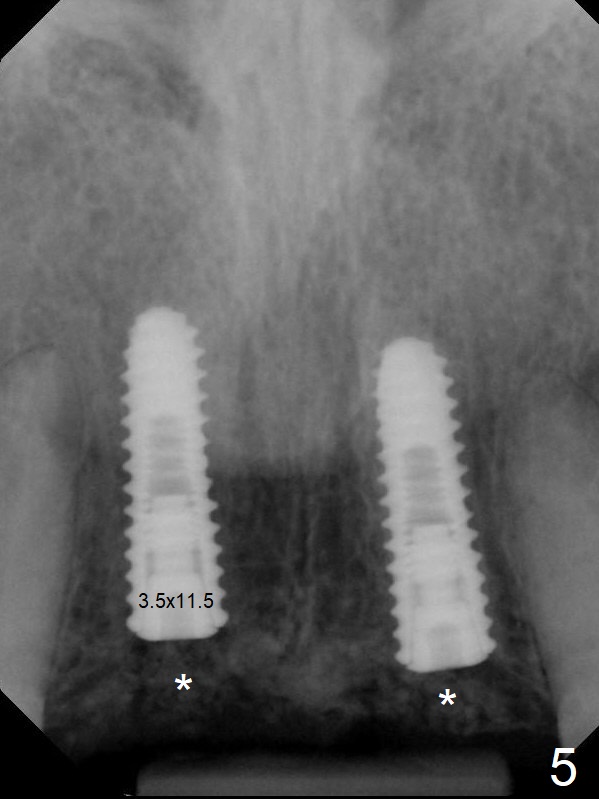

A 45-year-old Spanish woman requests implants to replace #7-10 FPD (Fig.1,2,7). After incision, osteotomy is initiated in the palatal aspect of the crest with 1.2 mm drill and DIO Bone Expanders (E1 (diameter 1.0/1.6 mm),E2 (1.3/2.3 mm), Fig.3,4). Following adjustment of the trajectory (to avoid invasion of the Incisive Canal (Fig.2 *) and use of E3 (1.7/3.1 mm), two of 3.5x11.5 mm HIOSSEN implants are placed with satisfactory stability (Fig.5). With Vanilla graft (Fig.5 *) placed over the palatally-exposed coronal threads, the flaps are approximated (Fig.6). The FPD is recemented temporarily (Fig.7).